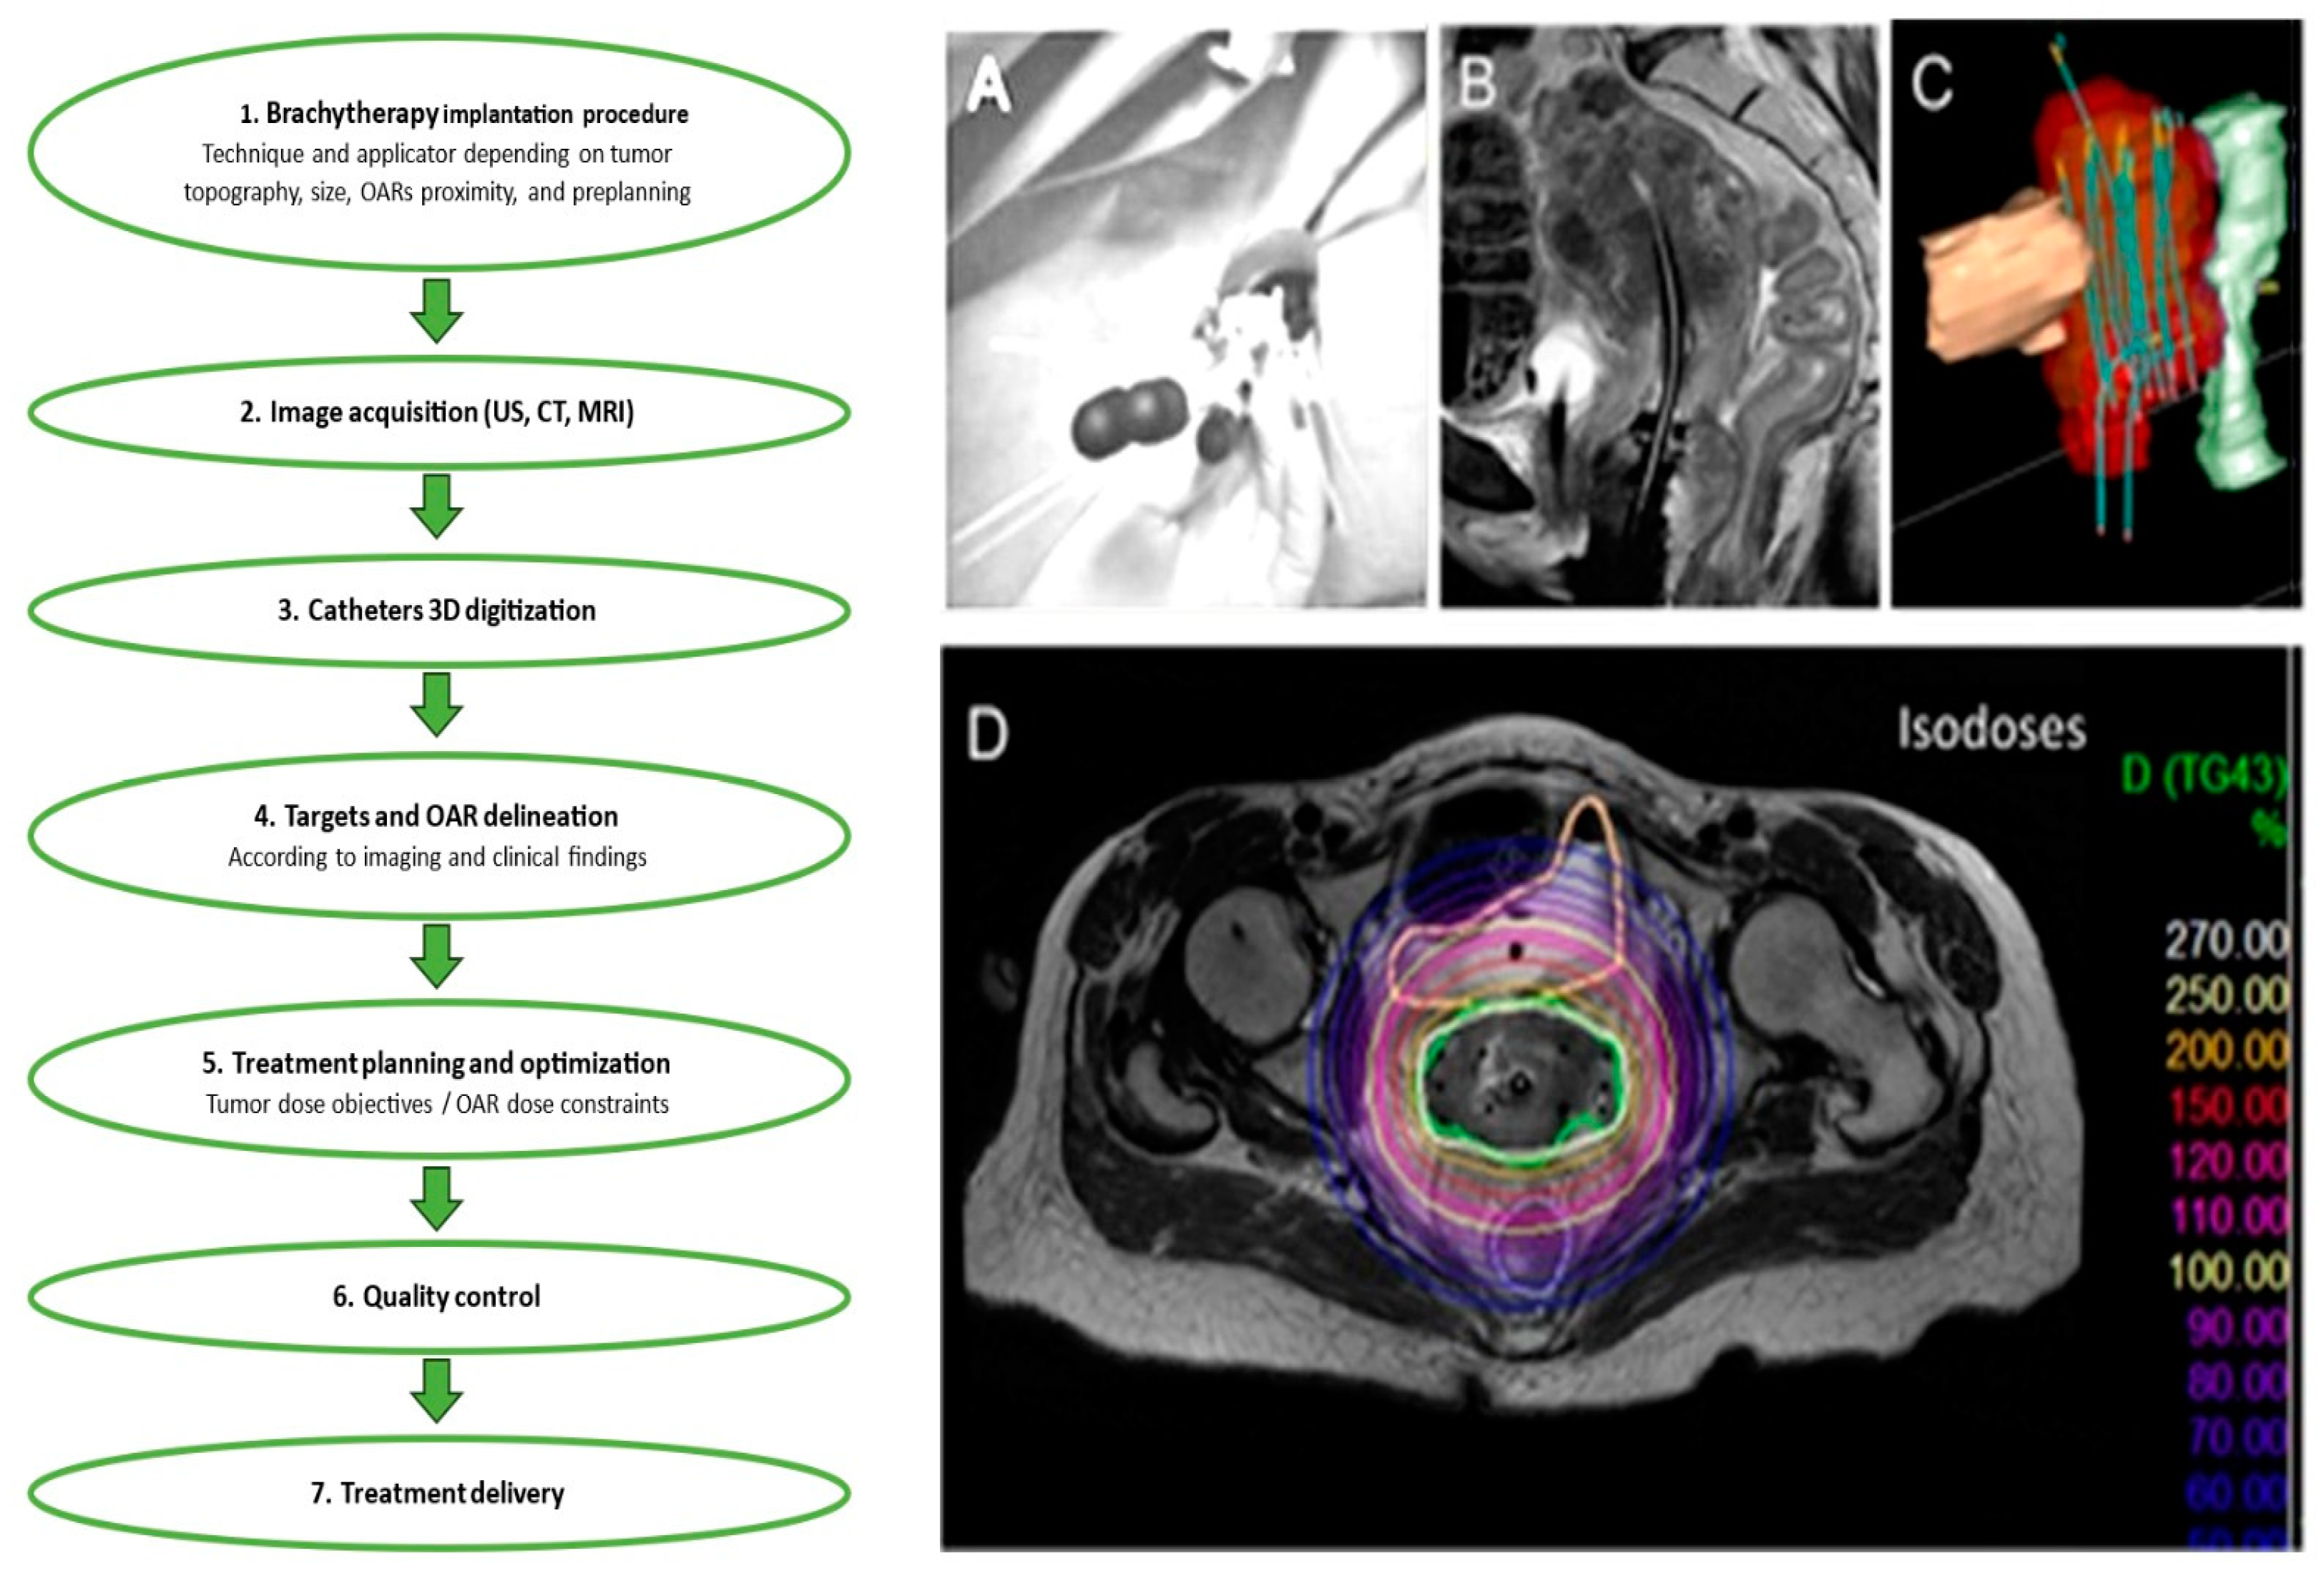

Figure 2. The illustration shows the steps that make up the brachytherapy procedure. This example shows how to: (A) perform an implantation; (B) acquire images; (C) digitize 3-dimensional (3D) catheters; and (D) demarcate targets and organs at risk (OARs). Treatment delivery, quality control, and treatment planning and optimization (D) come next.